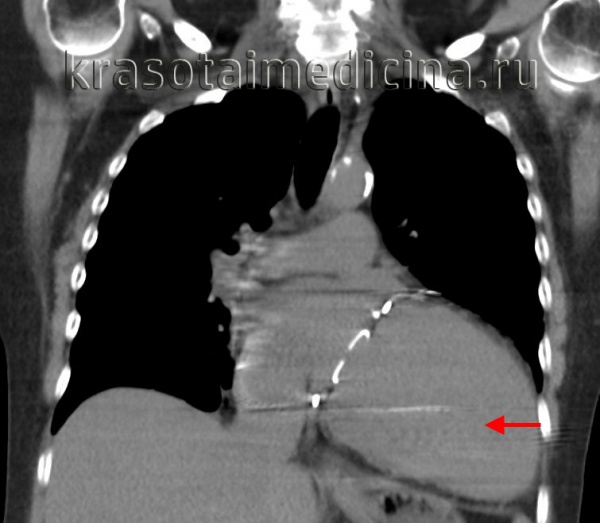

КТ органов грудной клетки. Выраженное расширение сердца (преимущественно левые отделы) у пациента с кардиомиопатией.

Рентгенологическое исследование. Признаки:

- увеличение размеров сердца за счет его левых отделов или чаще - тотальное, степень которого варьирует от относительно небольшой до резко выраженной по типу cor bovinum;

- тень сердца приобретает шаровидную форму; при значительном увеличении левого предсердия его конфигурация может приближаться к митральной;

- наряду с его дилатацией левого желудочка, как правило, отмечаются также признаки его гипертрофии;

- преобладание явлений венозного застоя со стороны сосудов малого круга кровообращения, более редко - признаки легочной артериальной гипертензии.